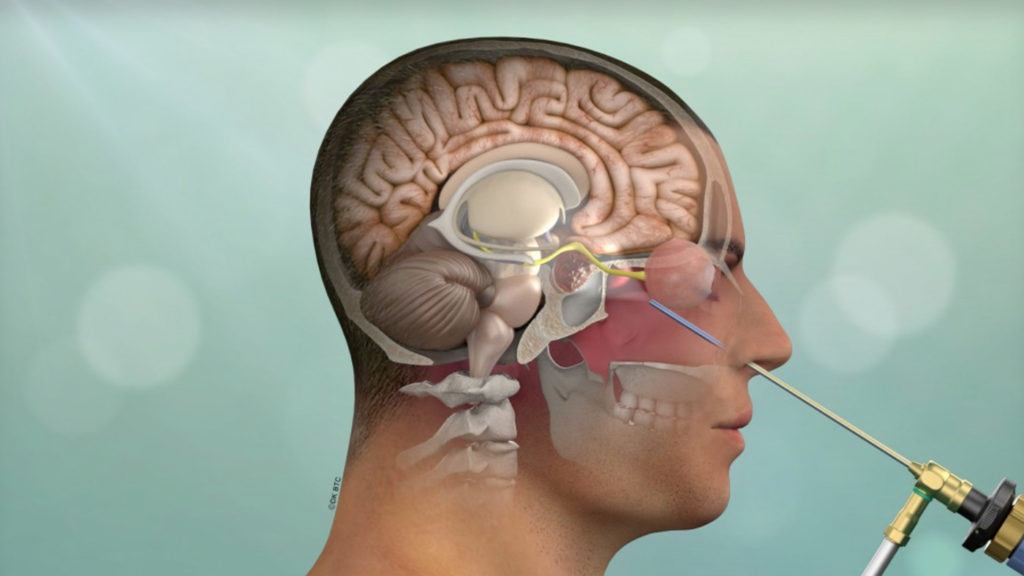

It is considered a minimally invasive brain surgery that allows neurosurgeons to identify and treat conditions that are deep within the brain.

Endoscopic spine surgery is a minimally invasive surgical procedure that uses a small, tubular instrument called an endoscope to visualize and treat various spinal conditions. The endoscope is inserted through a small incision, allowing surgeons to access and address issues in the spine with less tissue disruption than traditional open surgery.